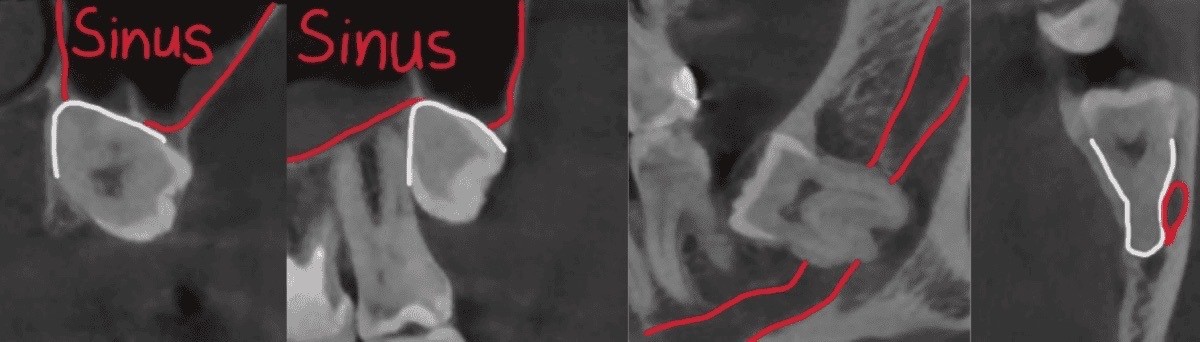

Kompyuter tomografiyasi va 3D rekonstruksiya natijalarida pastki aql tishi sohasida pastki jag‘ nervi ildizlarga juda yaqin joylashgani, yuqori tomonda esa tish yuqori jag‘ bo‘shlig‘i (gaymor bo‘shlig‘i) bilan chegaradosh ekanligi aniqlandi.

Bunday anatomik sharoitda olib tashlashning murakkabligi shundaki, pastki jag‘da operatsiyadan keyin lab va iyak terisining sezuvchanligi pasayishi mumkin, yuqorida esa gaymor bo‘shlig‘i bilan aloqa hosil bo‘lish xavfi mavjud.

• Mahalliy og‘riqsizlantirish ostida tishlarga jarrohlik kirish yo‘li yaratildi va ularni osonroq chiqarish uchun bir necha qismlarga ajratildi.

• Kattalashtirish nazorati ostida pastki jag‘ nerviga zarar yetkazmasdan va yuqorida gaymor bo‘shlig‘iga tegmasdan aql tishlari ehtiyotkorlik bilan olib tashlandi.